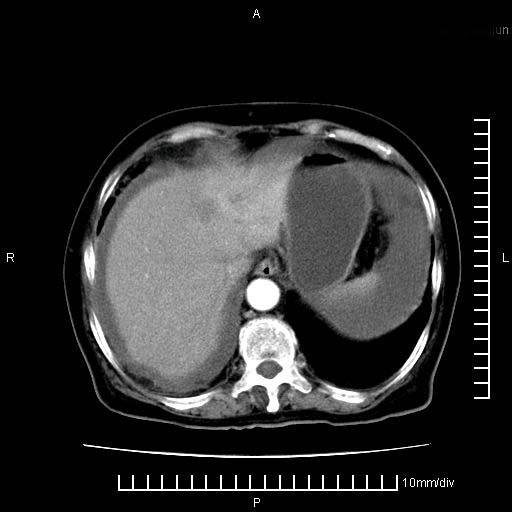

标题: CT28280:腹部增强:女性,80岁

上腹疼痛月余,外院核磁诊断胰腺癌。现临床示右下腹可明显触及包块,可片子上怎么没有看到?

1。胰腺ca伴腹膜腔转移

2。肝左叶低密度灶,考虑转移可能

支持胰腺癌肝内转移,腹水改变。

1、考虑胰腺癌伴腹膜腔转移,胸腹水。

2、肝脏转移可能。

1)考虑胰腺癌并胰腺假性囊肿形成。2)肝内低密度灶,不排除转移。3)右肾盂积水。4)腹水。5)右侧胸腔积液并右肺下叶部分膨胀不全。

考虑胰腺ca伴腹膜腔转移、肝左叶转移、右肾积水。右胸腔积液。